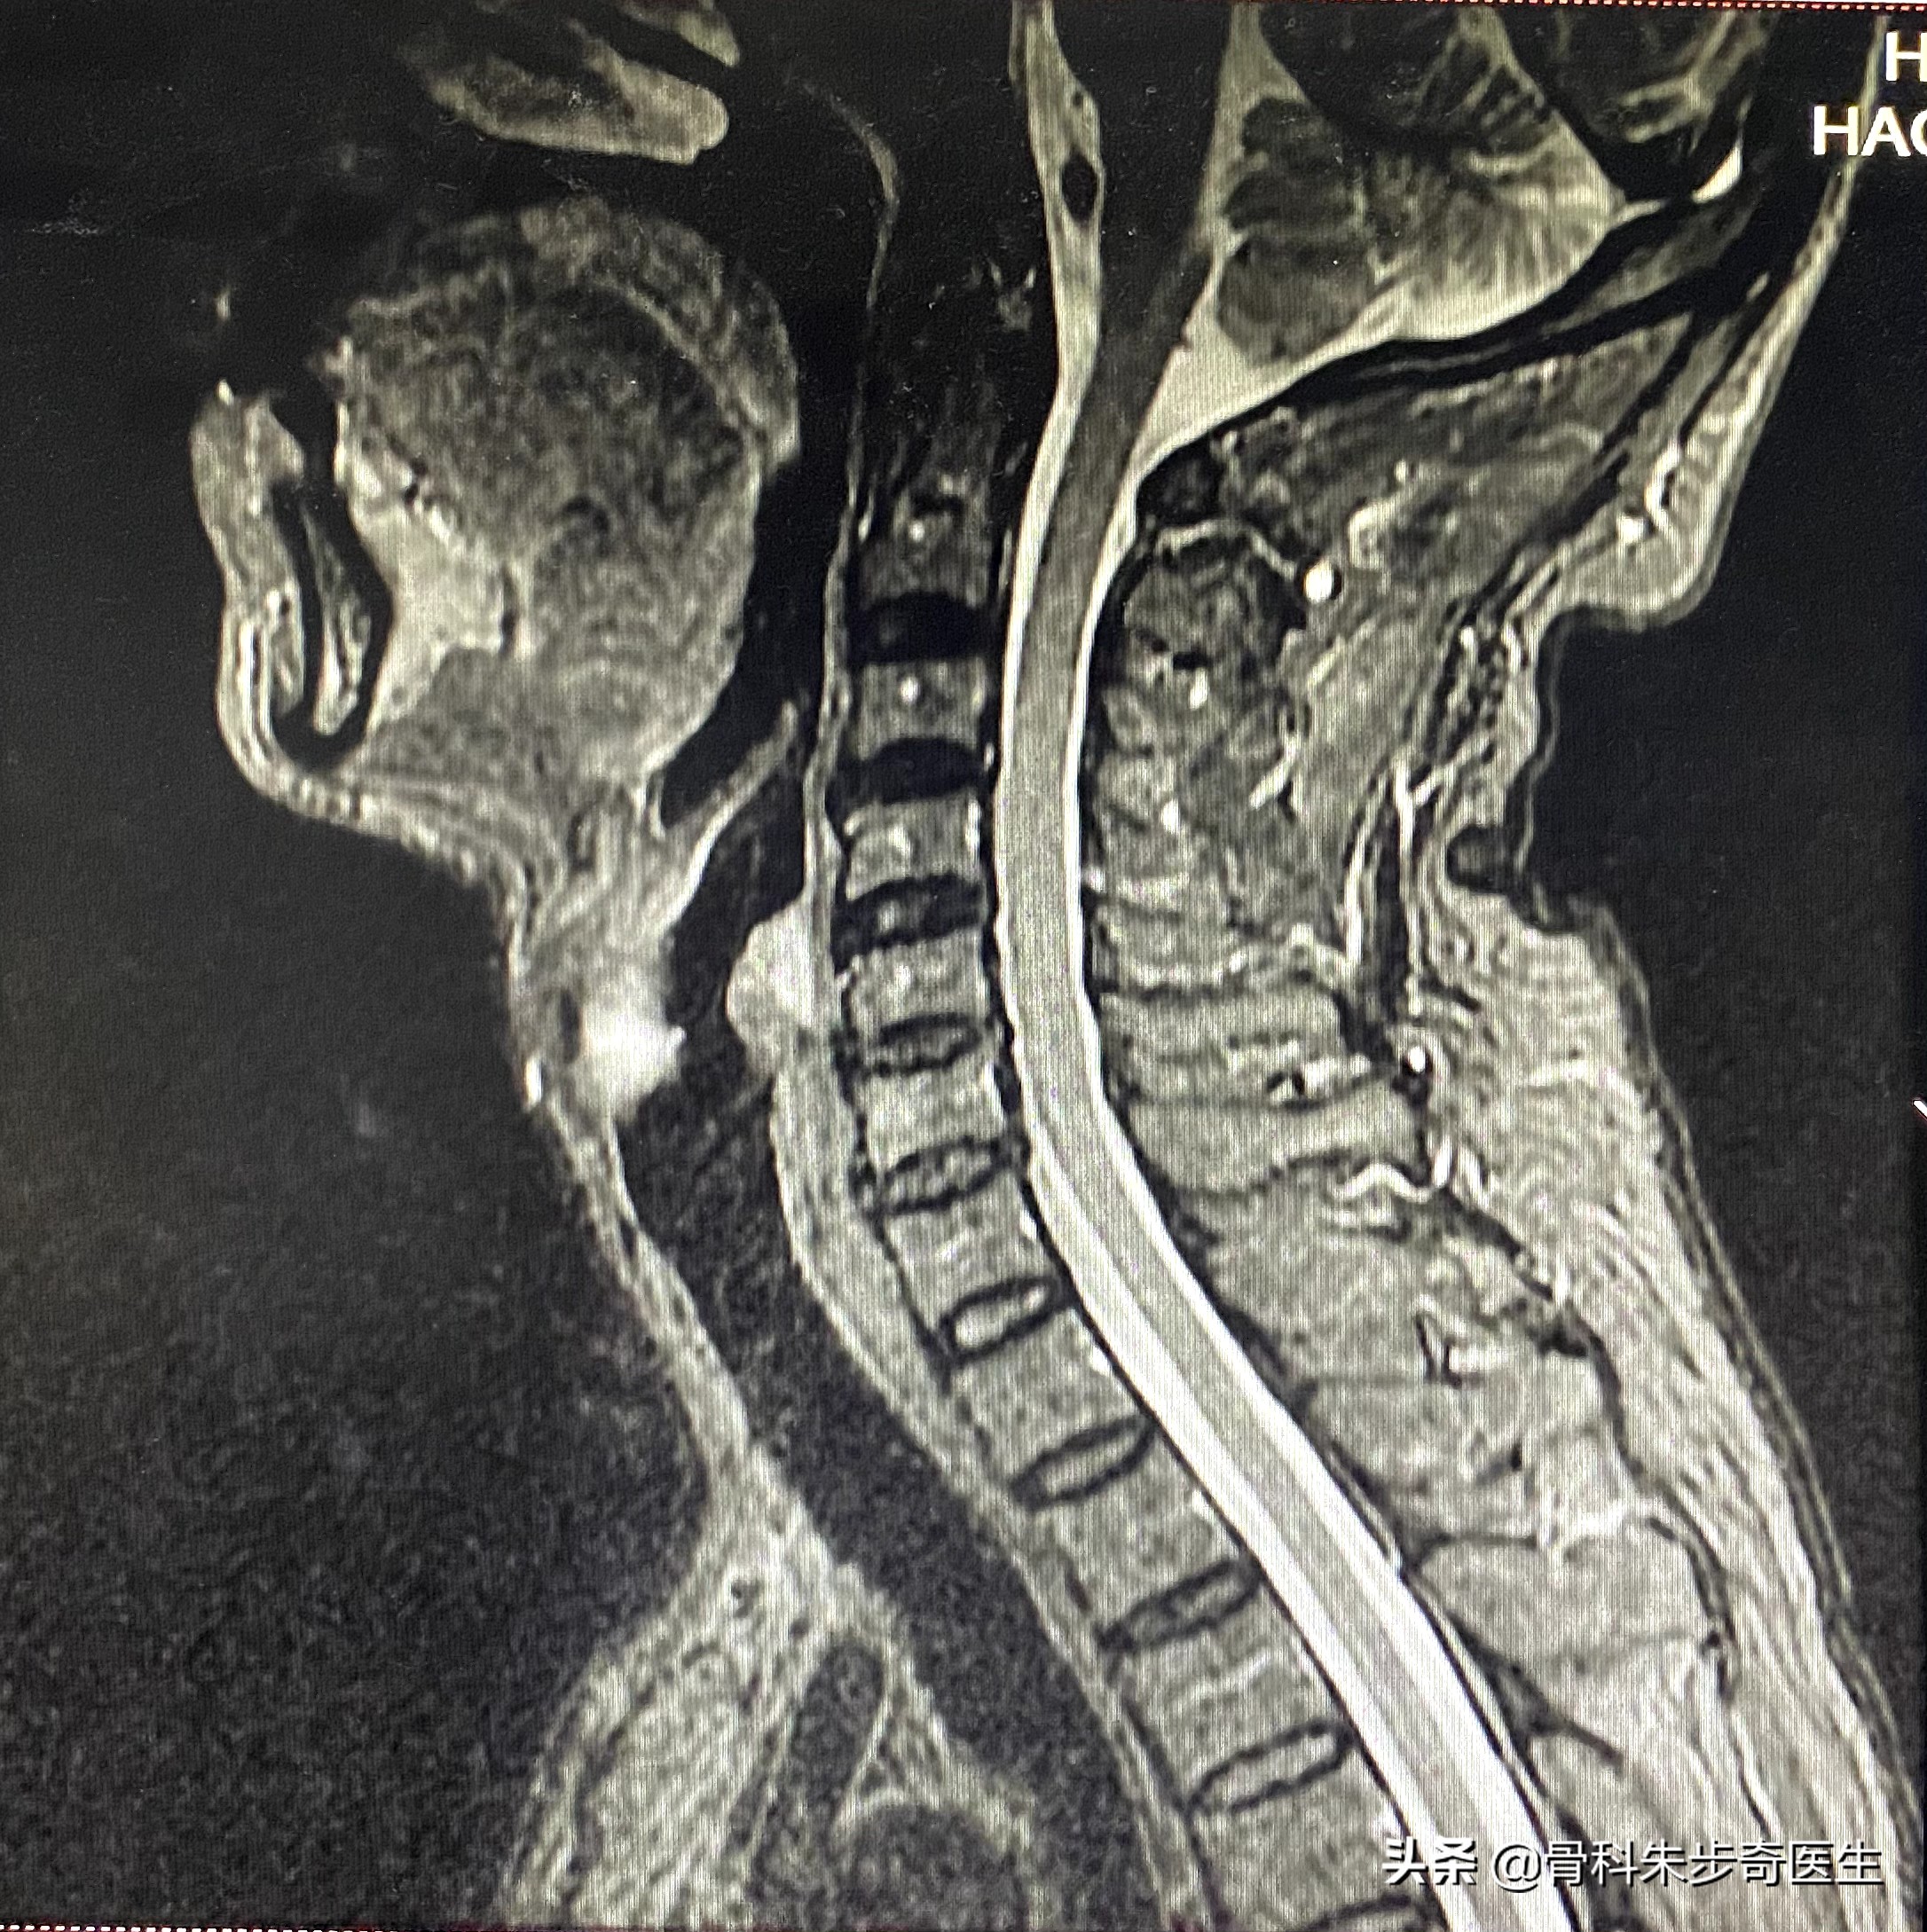

我问了一下他,这是什么片子,原来之前看过,做了一个磁共振,后来拿了片子后门诊医生已经下班了,他也找不到门诊医生了,所以今天来了,正好碰见我在门诊,我从系统当中调出来了他的片子,看了一下,结果如下:

其实这个片子上并看不到明显的压迫,前后的脊髓直径也都还可以,也没有椎间盘明显的突出,所以应该不是颈椎的问题。